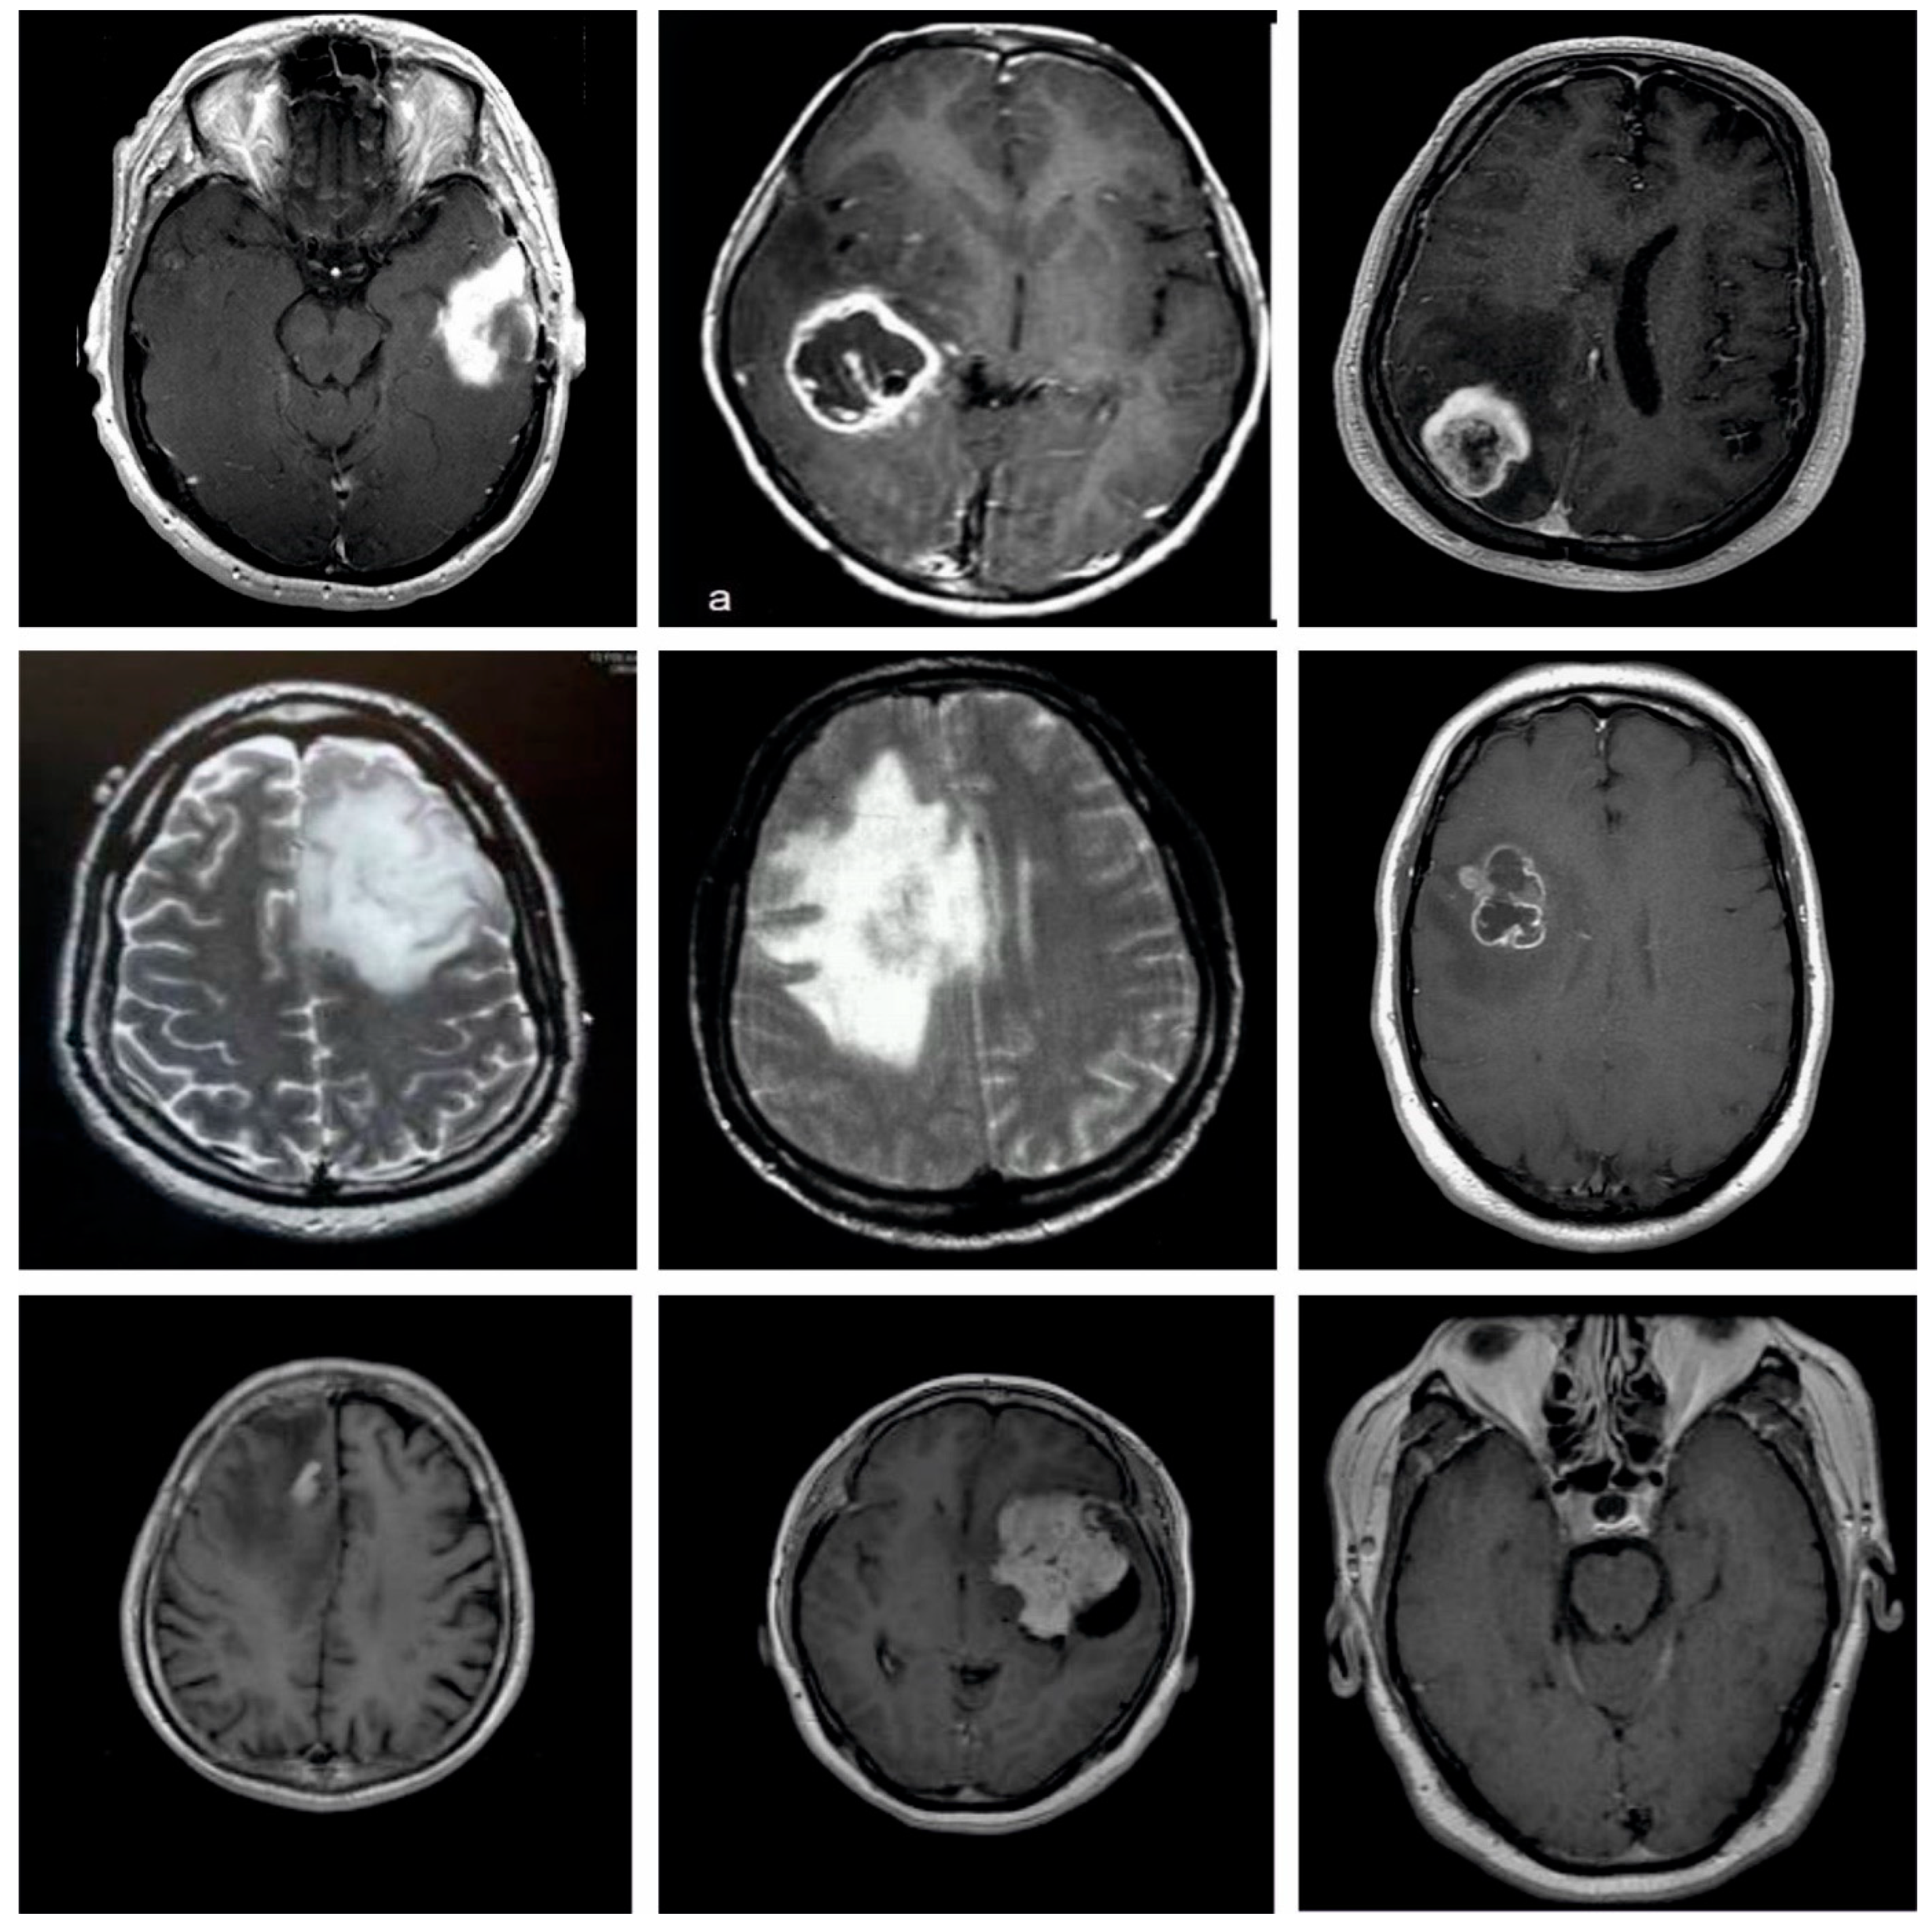

In this study, the performance validation of the EADL-BTMIC model is carried out using the Figshare dataset [24]. The details related to the dataset are shown in Table 1. A few sample images are illustrated in Figure 3. The dataset holds 3064 T1-weighted contrast-enhanced images with 3 kinds of BT. The dataset includes 708 images in the Meningioma class, 930 images in the Pituitary class, and 1426 images in the Glioma class. In this study, the experimental validation occurs in two distinct ways by splitting the dataset into two aspects based on the size of the training and testing data: 80% of training with 20% of testing data and 70% of training with 30% of testing data. The proposed model is simulated using Python 3.6.5 tool. The parameter settings are given as follows: learning rate: 0.01, dropout: 0.5, batch size: 5, epoch count: 50, and activation: ReLU.

Figure 3. Sample Images.

Applsci 12 07953 g003